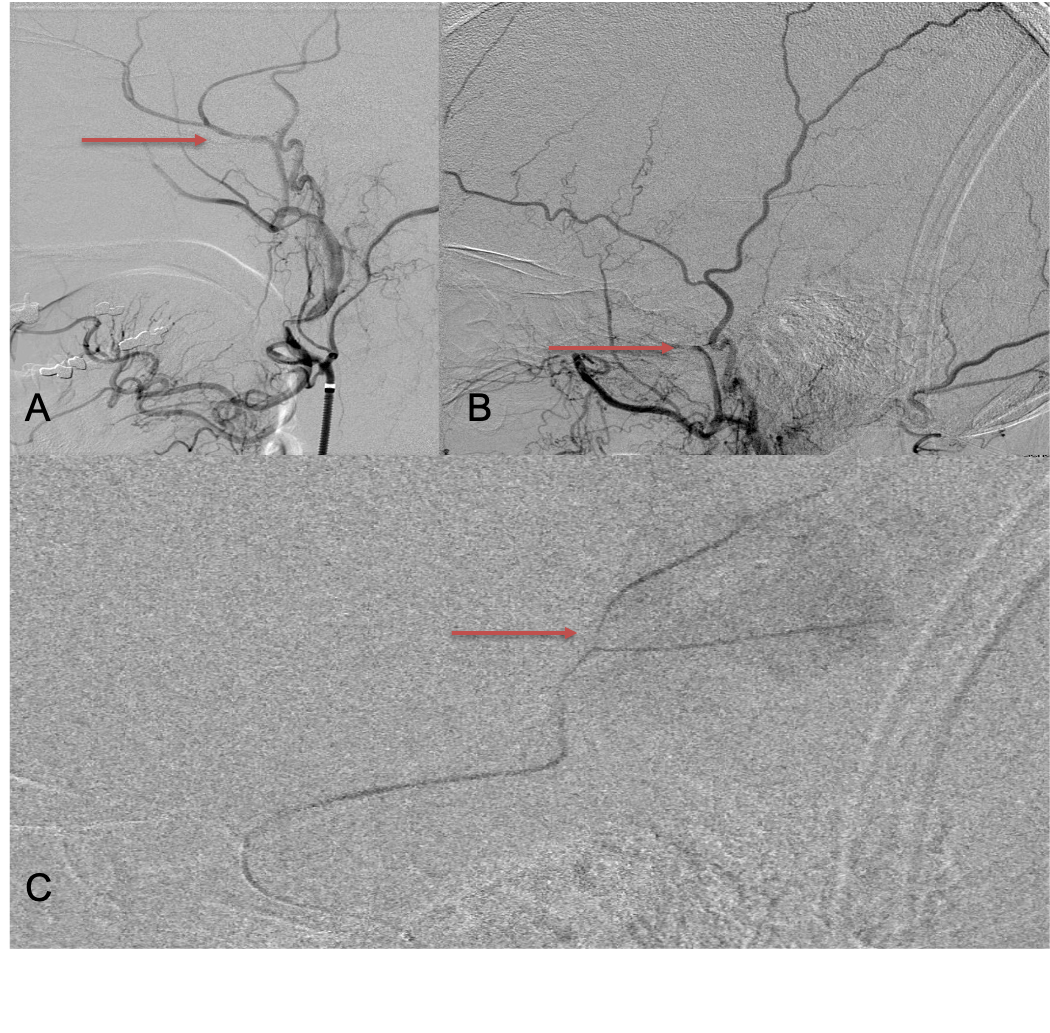

Clinically, the patient improved over the few weeks with the occasional transient twinge of a headache, but resolution of dizziness. Follow-up CT at 10 weeks demonstrated complete resolution of the bilateral subdural hematomas with our patient complete symptomatic and back to all of his activities of daily living. Considering his history of thrombocytopenia and CLL, we will continue to monitor him into the future and are excited about his progress and recovery. (Figure 4. A and B)

Figure 4. A and B) – 10 weeks following embolization demonstrates complete resolution of bilateral collections both acute and chronic.